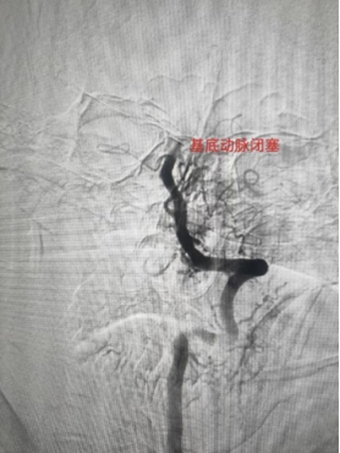

2、基底动脉栓塞,急诊导管抽栓+动脉溶栓1例;

0013.jpg

0014.jpg

0015.jpg

0016.jpg